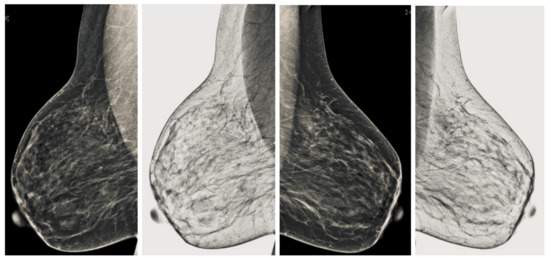

Figure 7.

Analysis of CC view of BI-RADS-1 mammogram images.

Figure 8.

Analysis of MLO view of BI-RADS-1 mammogram images.

We also measured the PSNR, the image contrast, and the EME of each category of databases, as we analyzed the image in terms of visual observation. The Table 3 shows the performance of our proposed image enhancement method. It can be seen from the Table 3 that our proposed method improved PSNR, contrast, and EME, and this also shows that our method can work on every category of BI-RADS. Because many techniques do not work on higher grade BI-RADS due to the complexity and the images are not of good quality. We obtained an average improvement in PSNR, contrast, and EME in the Table 4. For more observations, we analyzed the visual image of each category and we analyzed the CC and MLO of each category as shown in the Figure 7, Figure 8, Figure 9, Figure 10, Figure 11, Figure 12, Figure 13, Figure 14, Figure 15 and Figure 16. From the figures, every detail of image of every category can be observed, leading to better segmentation of the abnormal region. This image enhancement technique can be used as preprocessing steps for the detection of breast cancer. It is a very fast processing algorithm and it takes on 21.13 s. It gives opportunity to medical experts to analyze the mammogram images very quickly to propose the timely treatment.